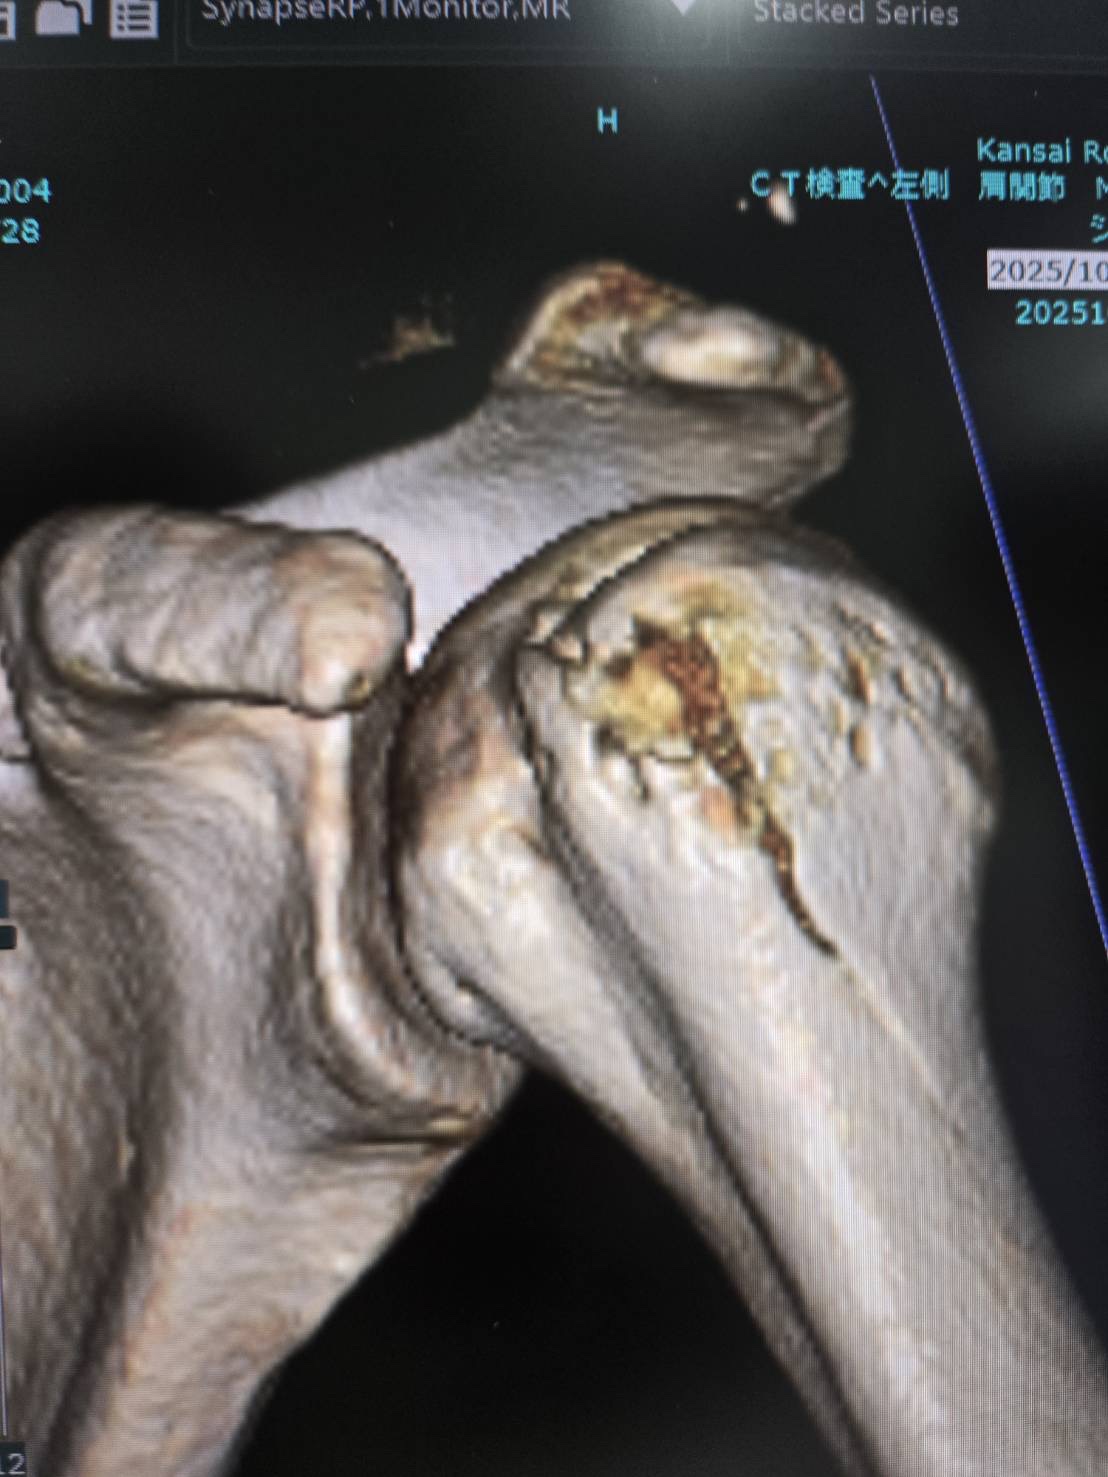

夜間救急でレントゲン(左肩・左肘・左股関節)を撮り、左肘の傷口は縫ってもらいました。ひとまず骨折の有無はその場ではっきりしなかったため、紹介状を書いてもらい大きな病院で精密検査を受けることにしました。

翌日、再度レントゲン・CT・MRIを撮った結果、左肩の骨にヒビが入っていることが判明しました…。

そこまで酷くはなかったため手術はせず、三角巾で固定して経過観察することに。今後ヒビが悪化すれば手術を検討する治療プランです。